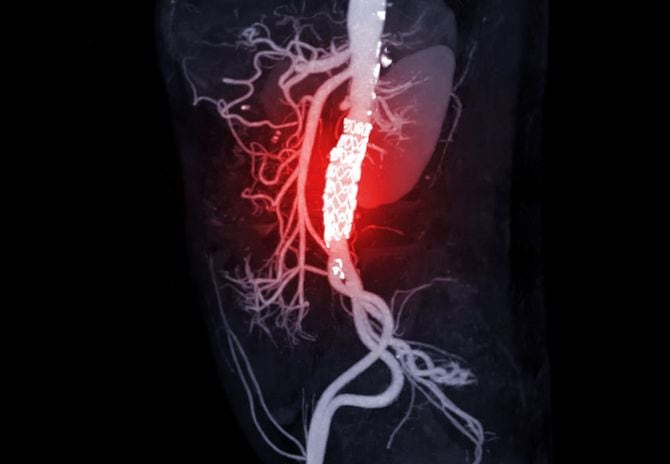

2019年11月、「ステントグラフト」という人工血管を挿入する手術以降、定期的に通院していた母親は、血液検査や尿検査の結果、腎機能が弱くなっていることを指摘される。